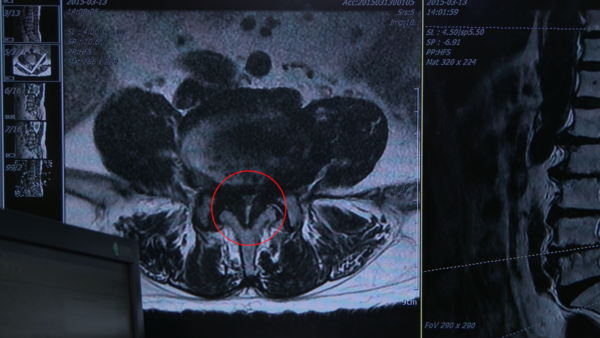

허리에 노화가 진행되면서 굳은 뼈가 자란다. 뼈와 뼈를 연결해주는 물렁뼈가 밀려나오고 인대가 부풀어지면서 신경이 지나가는 길을 좁게 만드는 것을 '척추관 협착증'이라 한다.

척추관 협착증의 대표적인 원인은 허리의 노화다. 나이가 들수록 허리 근력이 약해지고, 뼈를 잡아주는 인대들이 느슨해진다. 나이가 들면서 체중도 늘고, 허리에 직접적인 충격이 가해지면 퇴행성 변화가 일어나게 되면서 인대가 두꺼워져 뼈를 연결해주는 굳은 뼈들이 자라 들어와 신경관이 좁아지는 것이 척추관 협착증의 원인이다.